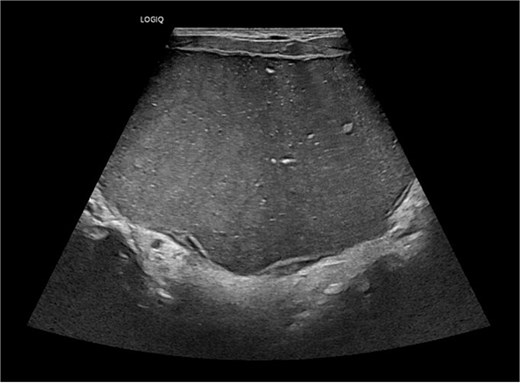

Ultrasound imaging demonstrated a large, well-defined cystic lesion arising from the floor of the mouth with displacement of the mylohyoid and intrinsic tongue musculature, without internal vascularity (Fig. 2). Fine-needle aspiration yielded cyst contents only, without further diagnostic information.

Ultrasound of neck showing large well defined cystic midline lesion involving floor of mouth.